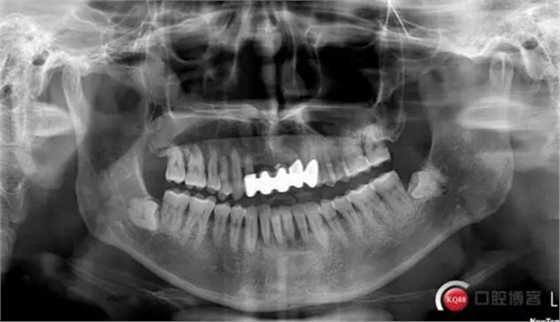

此患者为下颌前牙区松动牙试保留案例,牙周炎伴根尖周炎,并且31颊舌双根管。术中由于我的个人失误,导致整体治疗过程延长,特此总结,自我警醒。

检查:口腔卫生状况欠佳,牙面可见大量色素附着,牙石II°,尤以下颌前牙舌侧及后牙颊侧为重。牙龈红肿,BI3-4°,PD下颌前牙区4-6mm。31松动III°,温度测试无反应,叩不适。32、41、42松II°+,32温度测试迟钝,叩(-)。

X线示牙槽骨吸收,下颌前牙区可见龈下牙石影像,牙槽骨吸收至根尖1/3,根周透射影像。

诊断:慢性牙周炎

31慢性根尖周炎

32牙髓充血?慢性牙髓炎?